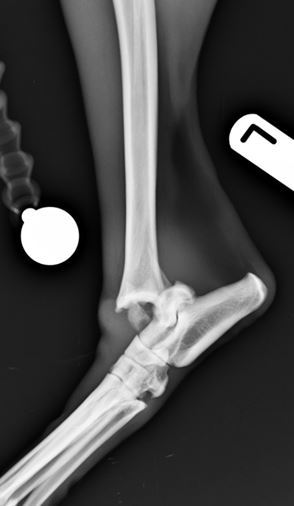

Radiographs revealed a comminuted non-reducible fracture of the medial talar ridge and a displaced fracture of the distal fibula.

Figure 1. Comminuted talar and distal fibular fractures lateral view